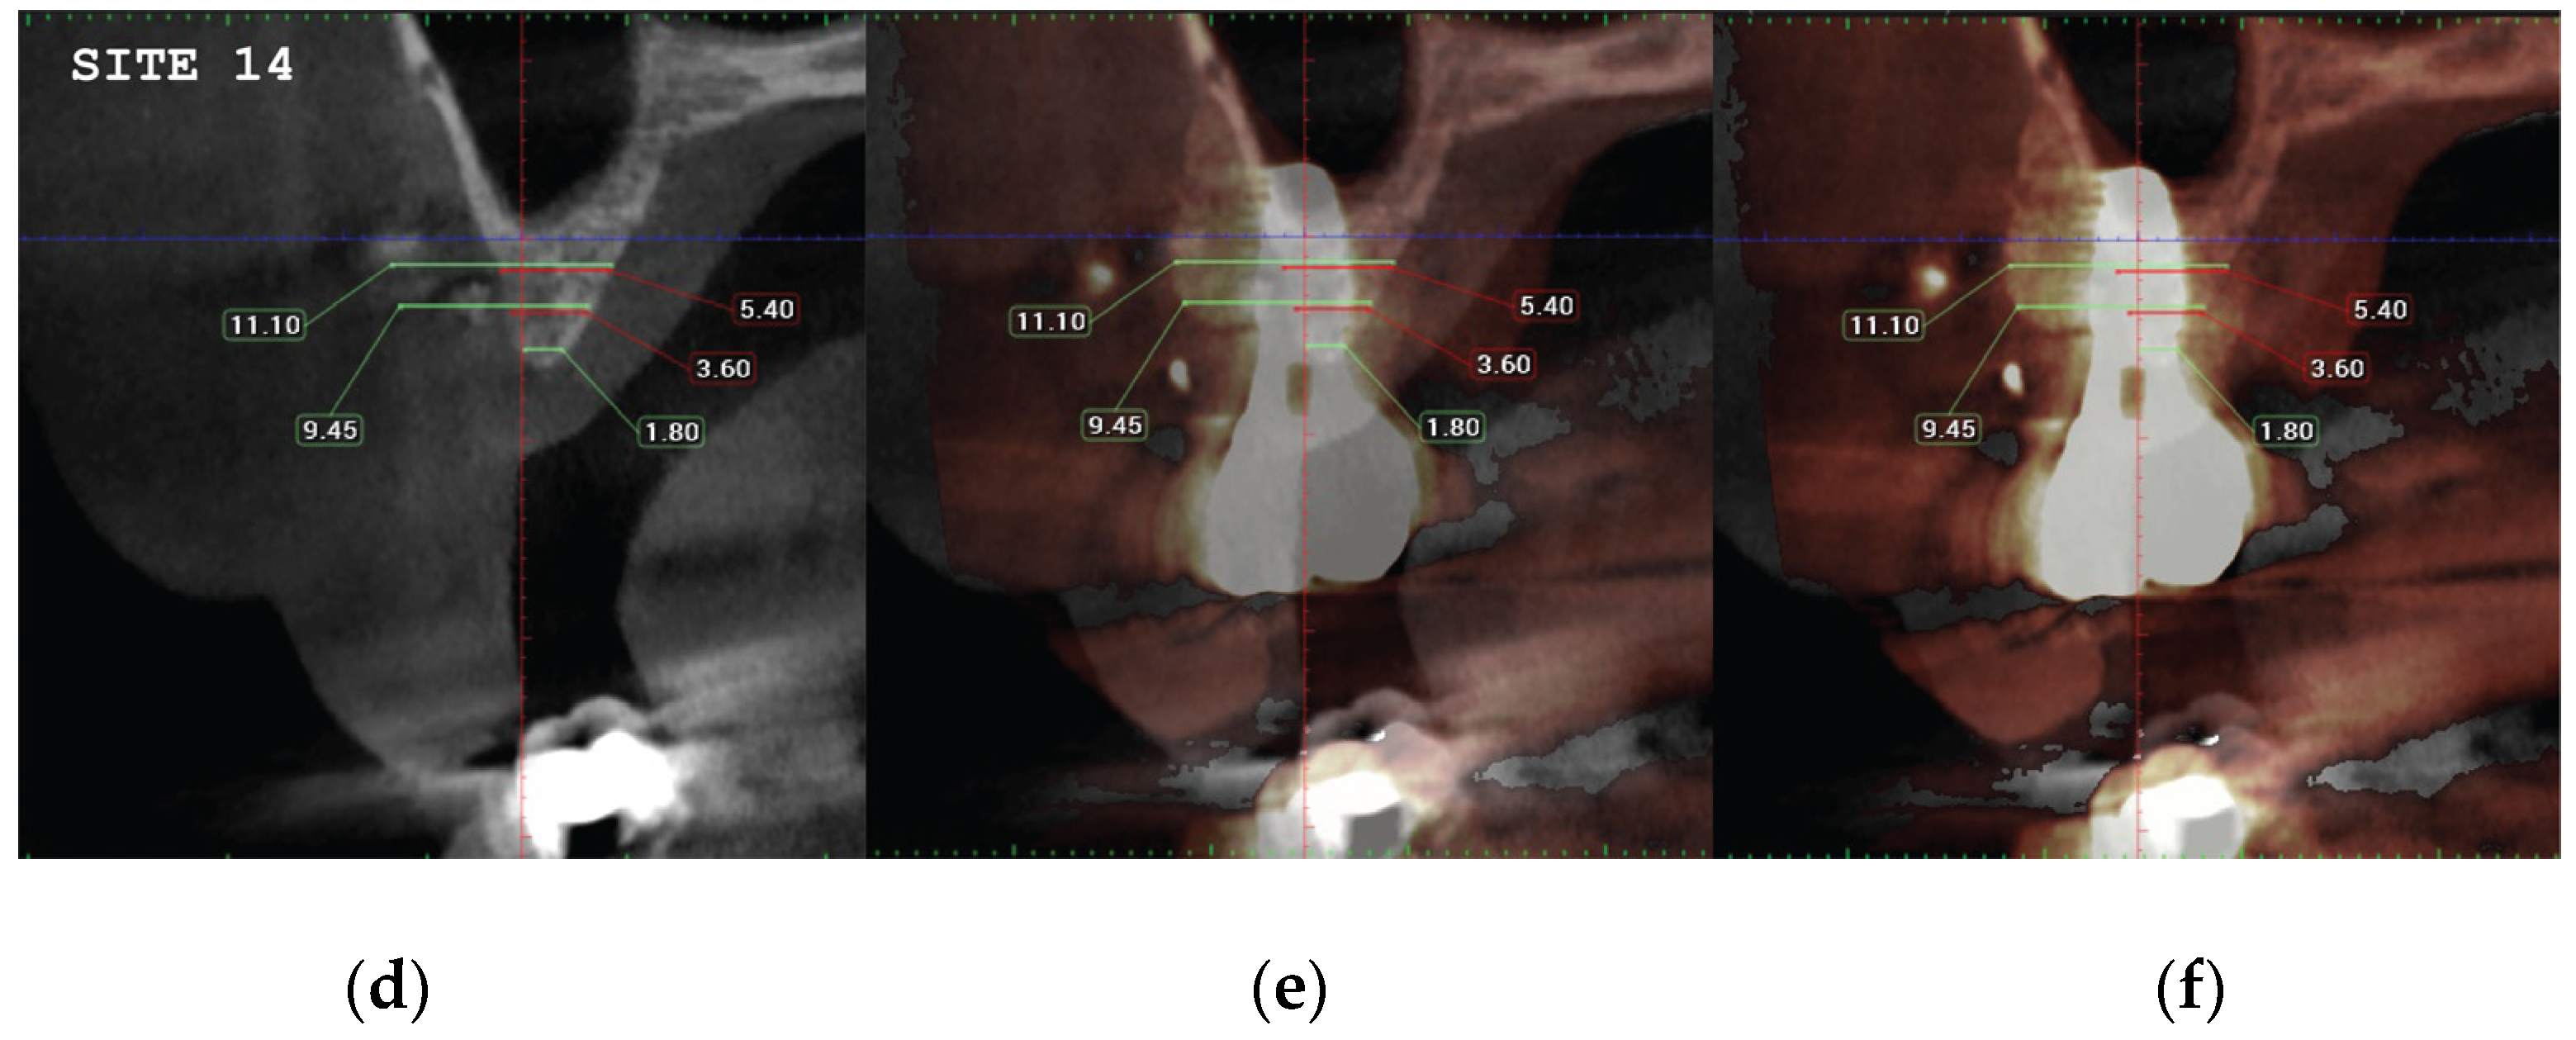

Data Collection

CBCT images were obtained using a CS8100 3D Carestream computed radiography system (Carestream Health, USA), at 0,150mm voxel size and field of view 8x9 cm prior (T1) and 16 weeks (T2) after implant placement. The original files in -DICOM format- were imported into the Romexis software (Planmeca Oy, Tuusula, Finland) for analysis. Both T1 and T2 datasets were superimposed in the software, using a point-based registration and if needed further manual alignment by an experienced oral imaging specialist. 2D measurements were acquired on both registered volumes where a slider tool could help hide and show the second superposed volume. First, measurements on T1 were done, after on T2. The cross-section in the middle of the site on the axial slice, and perpendicular to the alveolar crest was used to measure alveolar widths at 1mm, 3mm and 5mm heights (Figure 21, 22). An approximate Bone volume segmentation of the bone gain was performed on both volumes using a manual segmentation tool to visualize the gain in 3D (see Figure 23).

Significant gains in bone configuration were recorded via CBCT data collection and alveolar width measurements at 3 different levels of the ridge for both T1 and T2 datasets. Values at T2 for the 2 upper maxilla sites ranged from a minimum of 6.45mm to a maximum of 11.10mm with the highest difference T2-T1 recorded at the distal 14 site. Lower site values ranged from a minimum of 4.95 mm to a maximum of 9,75mm with the highest difference T2-T1 at the pontic site 35. Although these values were taken at different levels, if we consider that at least 1 to 2 mm of surrounding hard tissue are necessary for long term stability around dental implants, the current findings show exceptional hard tissue volume around all 4 implant sites. In particular, the value and importance of having a firm attachment and stabilization of the cortical barrier within the healing abutments platforms and over the overgrafted granulated material at a higher level that the one defined from the residual bony ridge at T1, is clearly demonstrated at the cross sectional CBCT images of the pontic site 35. Finally we may appreciate an overall 3D bone volume gain visualization at T2 after bone segmentation volume gains which confirm the results on the cross sectional images. Future studies could also include volumetric analysis on bone gains through STL files.

Figure 21. (a) the T1 CBCT image of 13 site, (b) the superposed images T1-T2, (c) and the.post image T2, with measurment overlaid. (d) (e) (f) Similar set-up for 14 premolar site.

Preprints 87073 g021aPreprints 87073 g021b